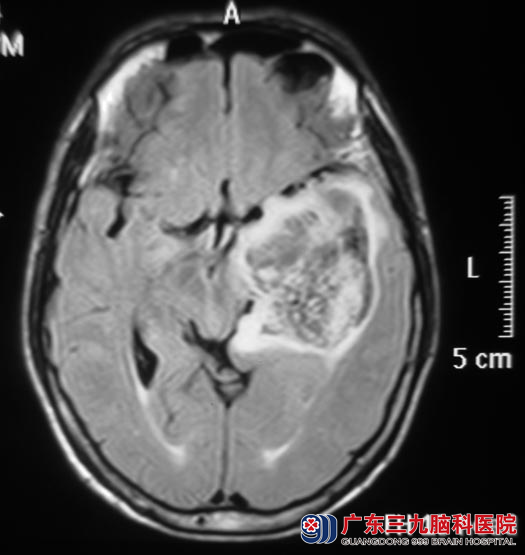

为寻求更专业的治疗,严先生入住广东三九脑科医院综合神经外科。头颅MR检查提示左侧颞叶占位性病变,局部轻度强化,考虑低级别胶质瘤,以弥漫性星型细胞瘤可能性大。

8月1日,鲁明主任主刀,在唤醒麻醉下行左侧颞叶、岛叶占位性病变切除术,术中见肿瘤性质稍韧,血供一般,唤醒麻醉后给予电生理监测,避开语言中枢,在显微镜下予左侧颞叶、岛叶肿瘤切除,术中对大脑前及大脑后动脉保护完好,严先生的语言及肢体运动功能均保护完好,手术顺利结束。复查头颅MRI结果提示:左侧颞叶及岛叶占位基本全切。术后经过治疗,患者康复出院。术后病理结果为:节细胞型胶质瘤(WHO II级)。